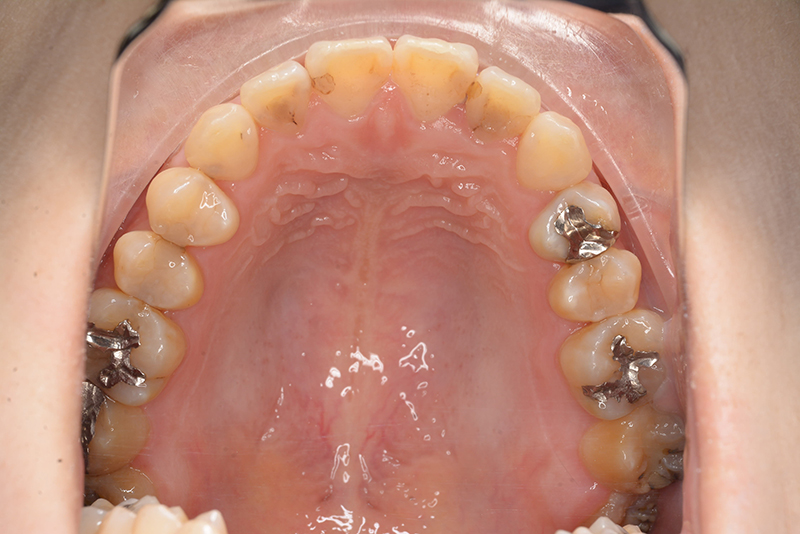

初診時

FP・IOP

主訴 受け口 診断名 アングルⅢ級反対咬合症例

口腔内所見 臼歯関係はⅢ級、下顎歯列はスピーカーブによって前歯は舌側へ倒れこみつつ挺出しておりover jet-2.5mm、over bite3.0mmと反対咬合を呈していた。